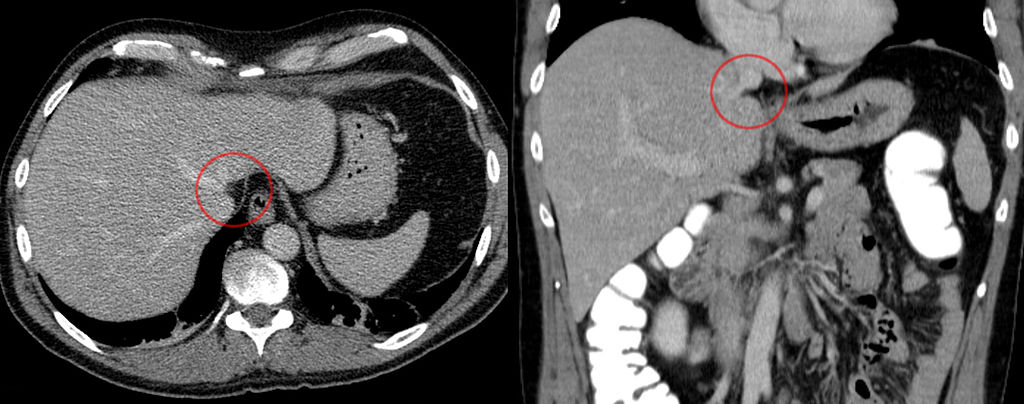

Entre los procedimientos más frecuentes se encuentra la radiografía preoperatoria, el análisis de diagnóstico por imágenes, las resonancias magnéticas etc. En el caso de que el lipoma sea grande, tenga un aspecto inusual o sea más profundo de lo normal, se puede realizar una exploración por TC que significa 'Tomografía computarizada'.